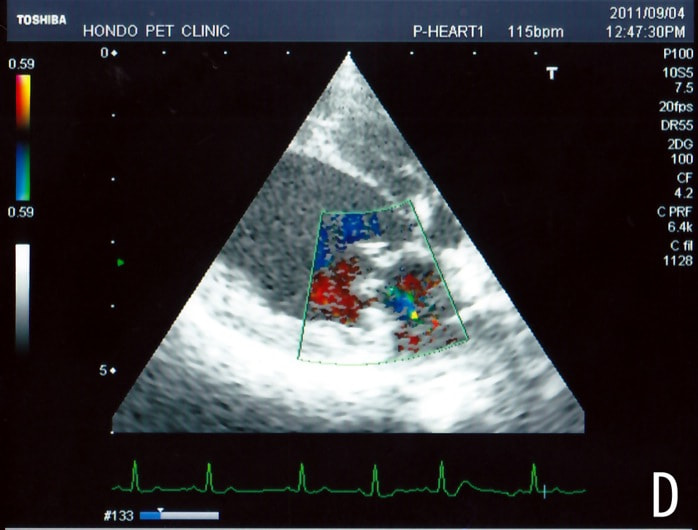

症例1:閉塞型肥大型心筋症(HOCM)【アメリカン・ショートヘア 4歳齢 去勢オス】

C:超音波写真 僧帽弁逆流と左室流出路狭窄

1年ほど前より左側胸壁からLevine 3/6の心雑音が聴取されていた。雑音の精査のため、心エコー検査を行ったところ、左室流出路の狭窄を伴う肥大型心筋症(閉塞型肥大型心筋症)と判明した。心室の拡張性を上げるため、βブロッカーであるカルベジロールを用いた治療を行っている。肥大型心筋症は犬の心疾患のように、心拡大を認めないことも多く、レントゲン写真のみで心疾患の有無を判断する事が出来ない。また、閉塞を伴わない肥大型心筋症と異なり、閉塞型の本疾患の治療に対し、Caチャネルブロッカーは推奨されない。